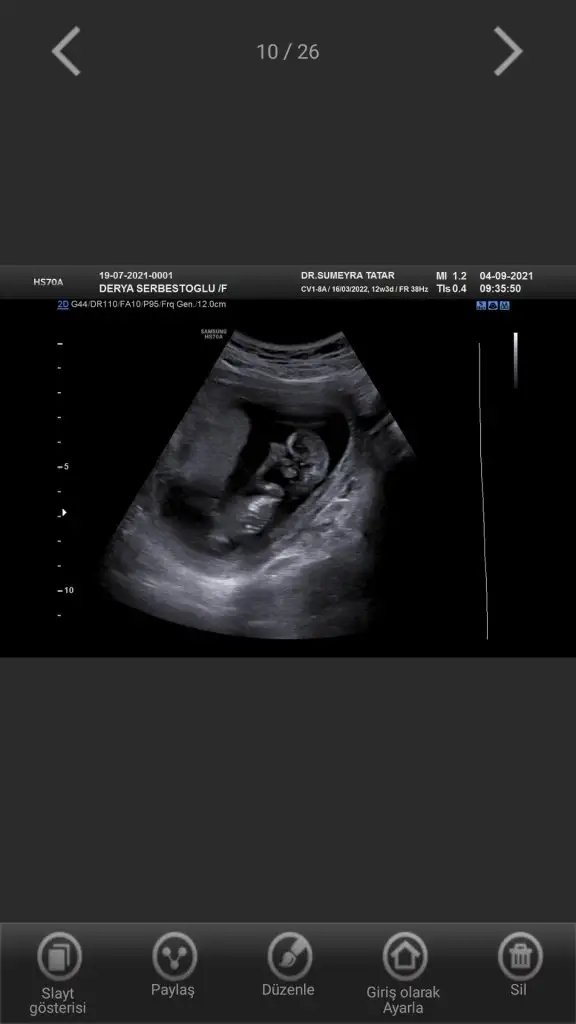

Canım bi bakar mısın yandan net görüntü yok maalesef 18 haftalık doktor erkek dedi ikinci resimde işaretlediği kısma pipi dedi sence de erkek mi bundan önce ki doktor kıza benzetmiştiKız gibi

Canım bakar mısın benim attığımı daCanım bi bakar mısın yandan net görüntü yok maalesef 18 haftalık doktor erkek dedi ikinci resimde işaretlediği kısma pipi dedi sence de erkek mi bundan önce ki doktor kıza benzetmişti

Ben 11 12 13 haftalar bakiyorum varsa paylaşınCanım bi bakar mısın yandan net görüntü yok maalesef 18 haftalık doktor erkek dedi ikinci resimde işaretlediği kısma pipi dedi sence de erkek mi bundan önce ki doktor kıza benzetmişti

Emin olamadım sanki erkek gibi

Doktor da emin değil ama erkek gibi sanki dediEmin olamadım sanki erkek gibi

Erkek görünüyorMerhaba bana da tahmin yapabilir misiniz?